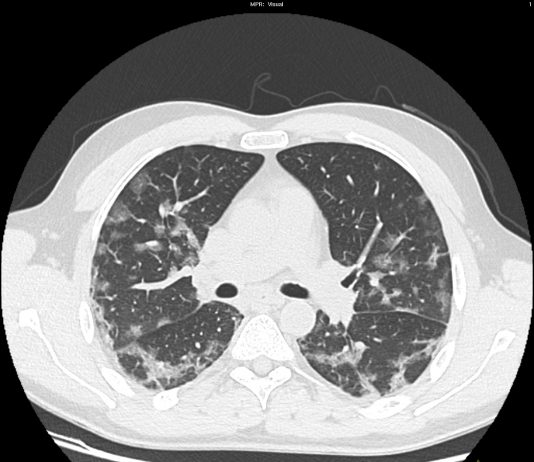

60-year-old male patient with fever for three days, coming from the “high-risk” zone. RT-PCR test positive

HRCT